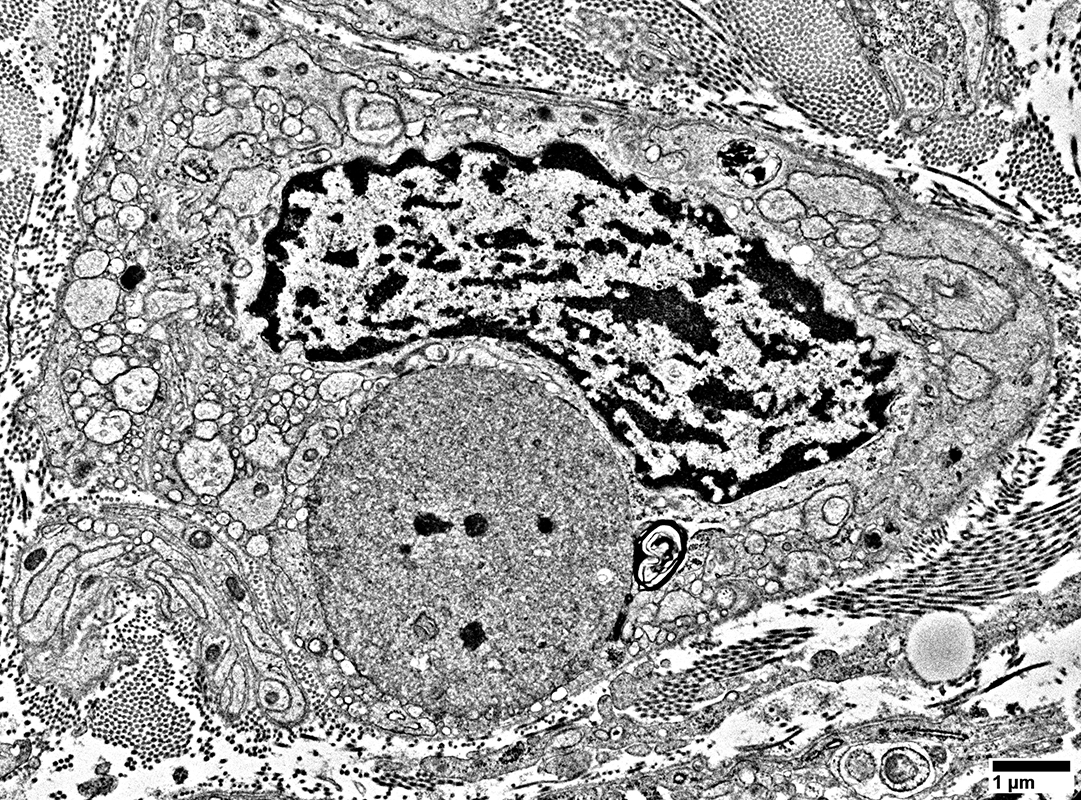

Schwann Cells

Some contain Lipid debris

Myelin Damage: Lipid Droplets & Ovoids in Schwann cells

Myelin Damage: Lipid Droplets & Myelin debris in Schwann cells

Myelin Damage: Lipid Droplets & some Myelin debris in Schwann cells

Lipid Droplets & Myelin debris segregated in different Schwann cell processes